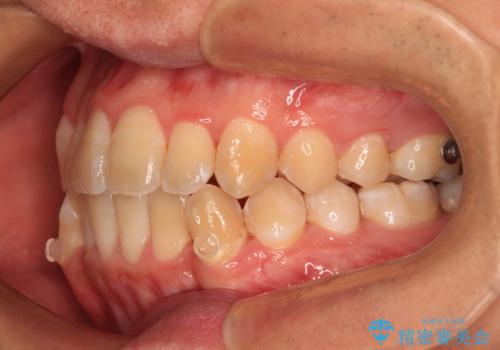

オープンバイトをインビザラインで矯正治療

- 前歯の開咬を気にして来院された患者様です。

開咬の治療は、前歯を閉じるように動かすとともに、上下臼歯を圧下(骨内にめり込ませる)させることで進めて行きます。

インビザラインは臼歯の圧下を効果的に行えるため、インビザラインを用いて矯正治療を行うこととしました。